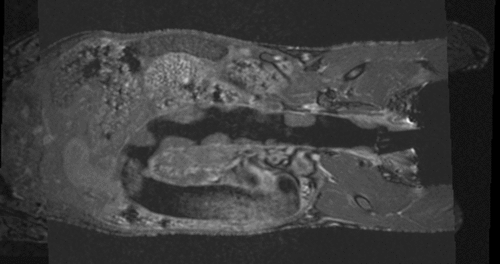

v3.6.1 Slicer3-6Announcement-v1.png Slicer Registration Library Case #35: Mouse Colon Brain MRI

case A lleft case B

fixed image 1/target

MRI mouse 1

moving image

MRI mouse 2

• reference/fixed MRI: 0.12 x 0.12 x 0.1 mm, 512 x 512 x 94

• moving MRI: 0.09 x 0.09 x 0.1 mm, 512 x 512 x 94